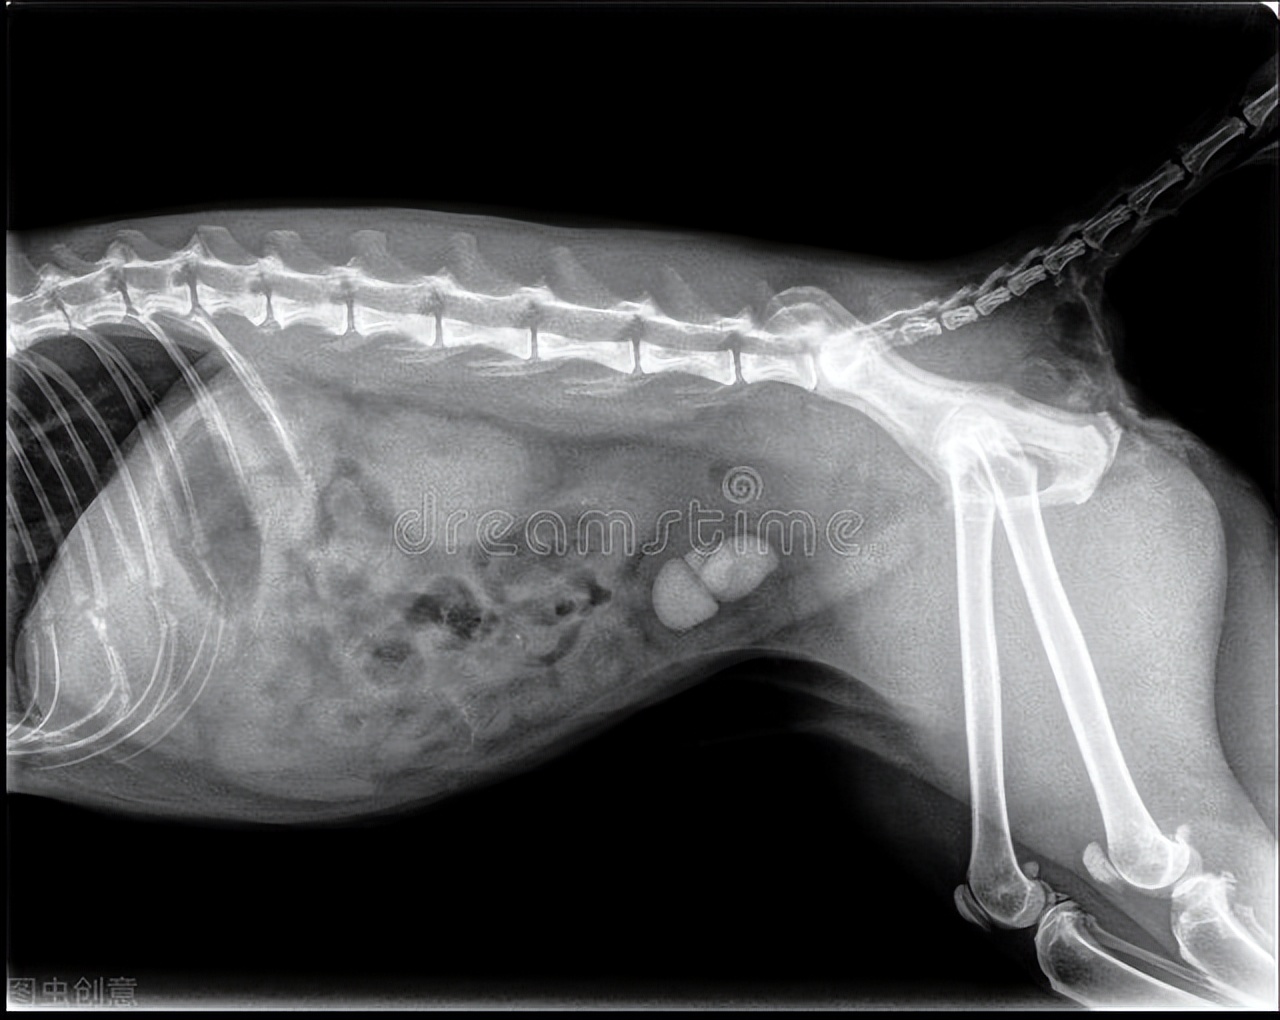

2:X光和B超辅助成像,直接查看泌尿道情况。

病情严重的,通过尿液检查、血液检查、X光检查出结石数量比较多且结石直径大,出现了闭尿或者严重尿血的,可以配合医生进行外科手术。